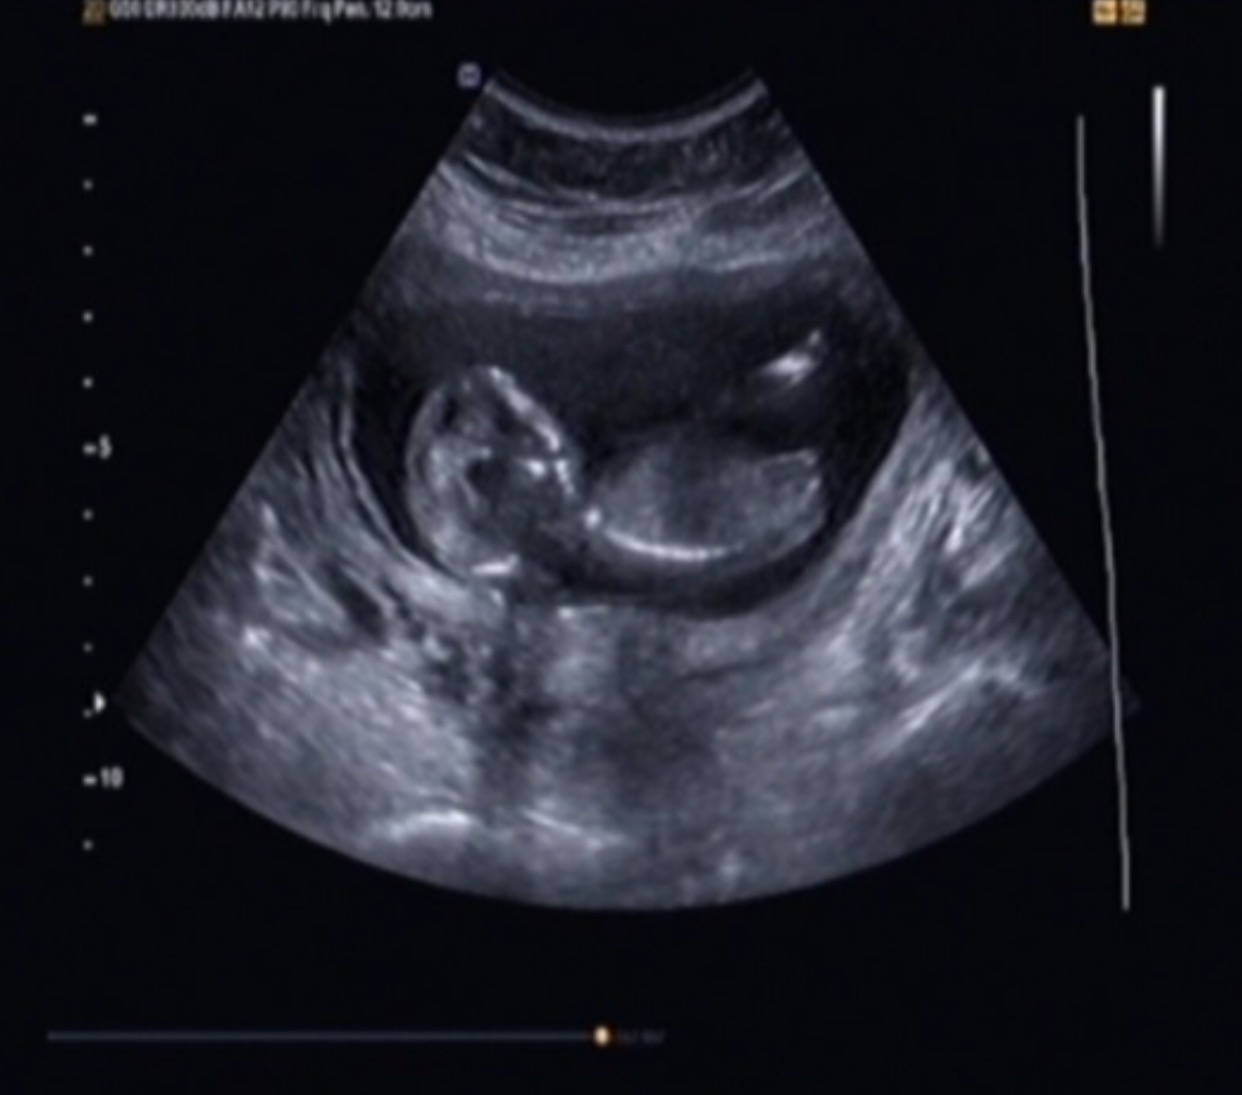

But I have had two scans, and told girl twice. Once the tech was extremely confident and said she wouldnt have said anything at all if she wasnt sure. The second tech said she was pretty sure she saw labia but our little one didnt want open her legs much at all that scan. I have pics from both scans that I want to post that include potty shots and nubs. Input?

Attachment 28271Attachment 28272Attachment 28273Attachment 28274